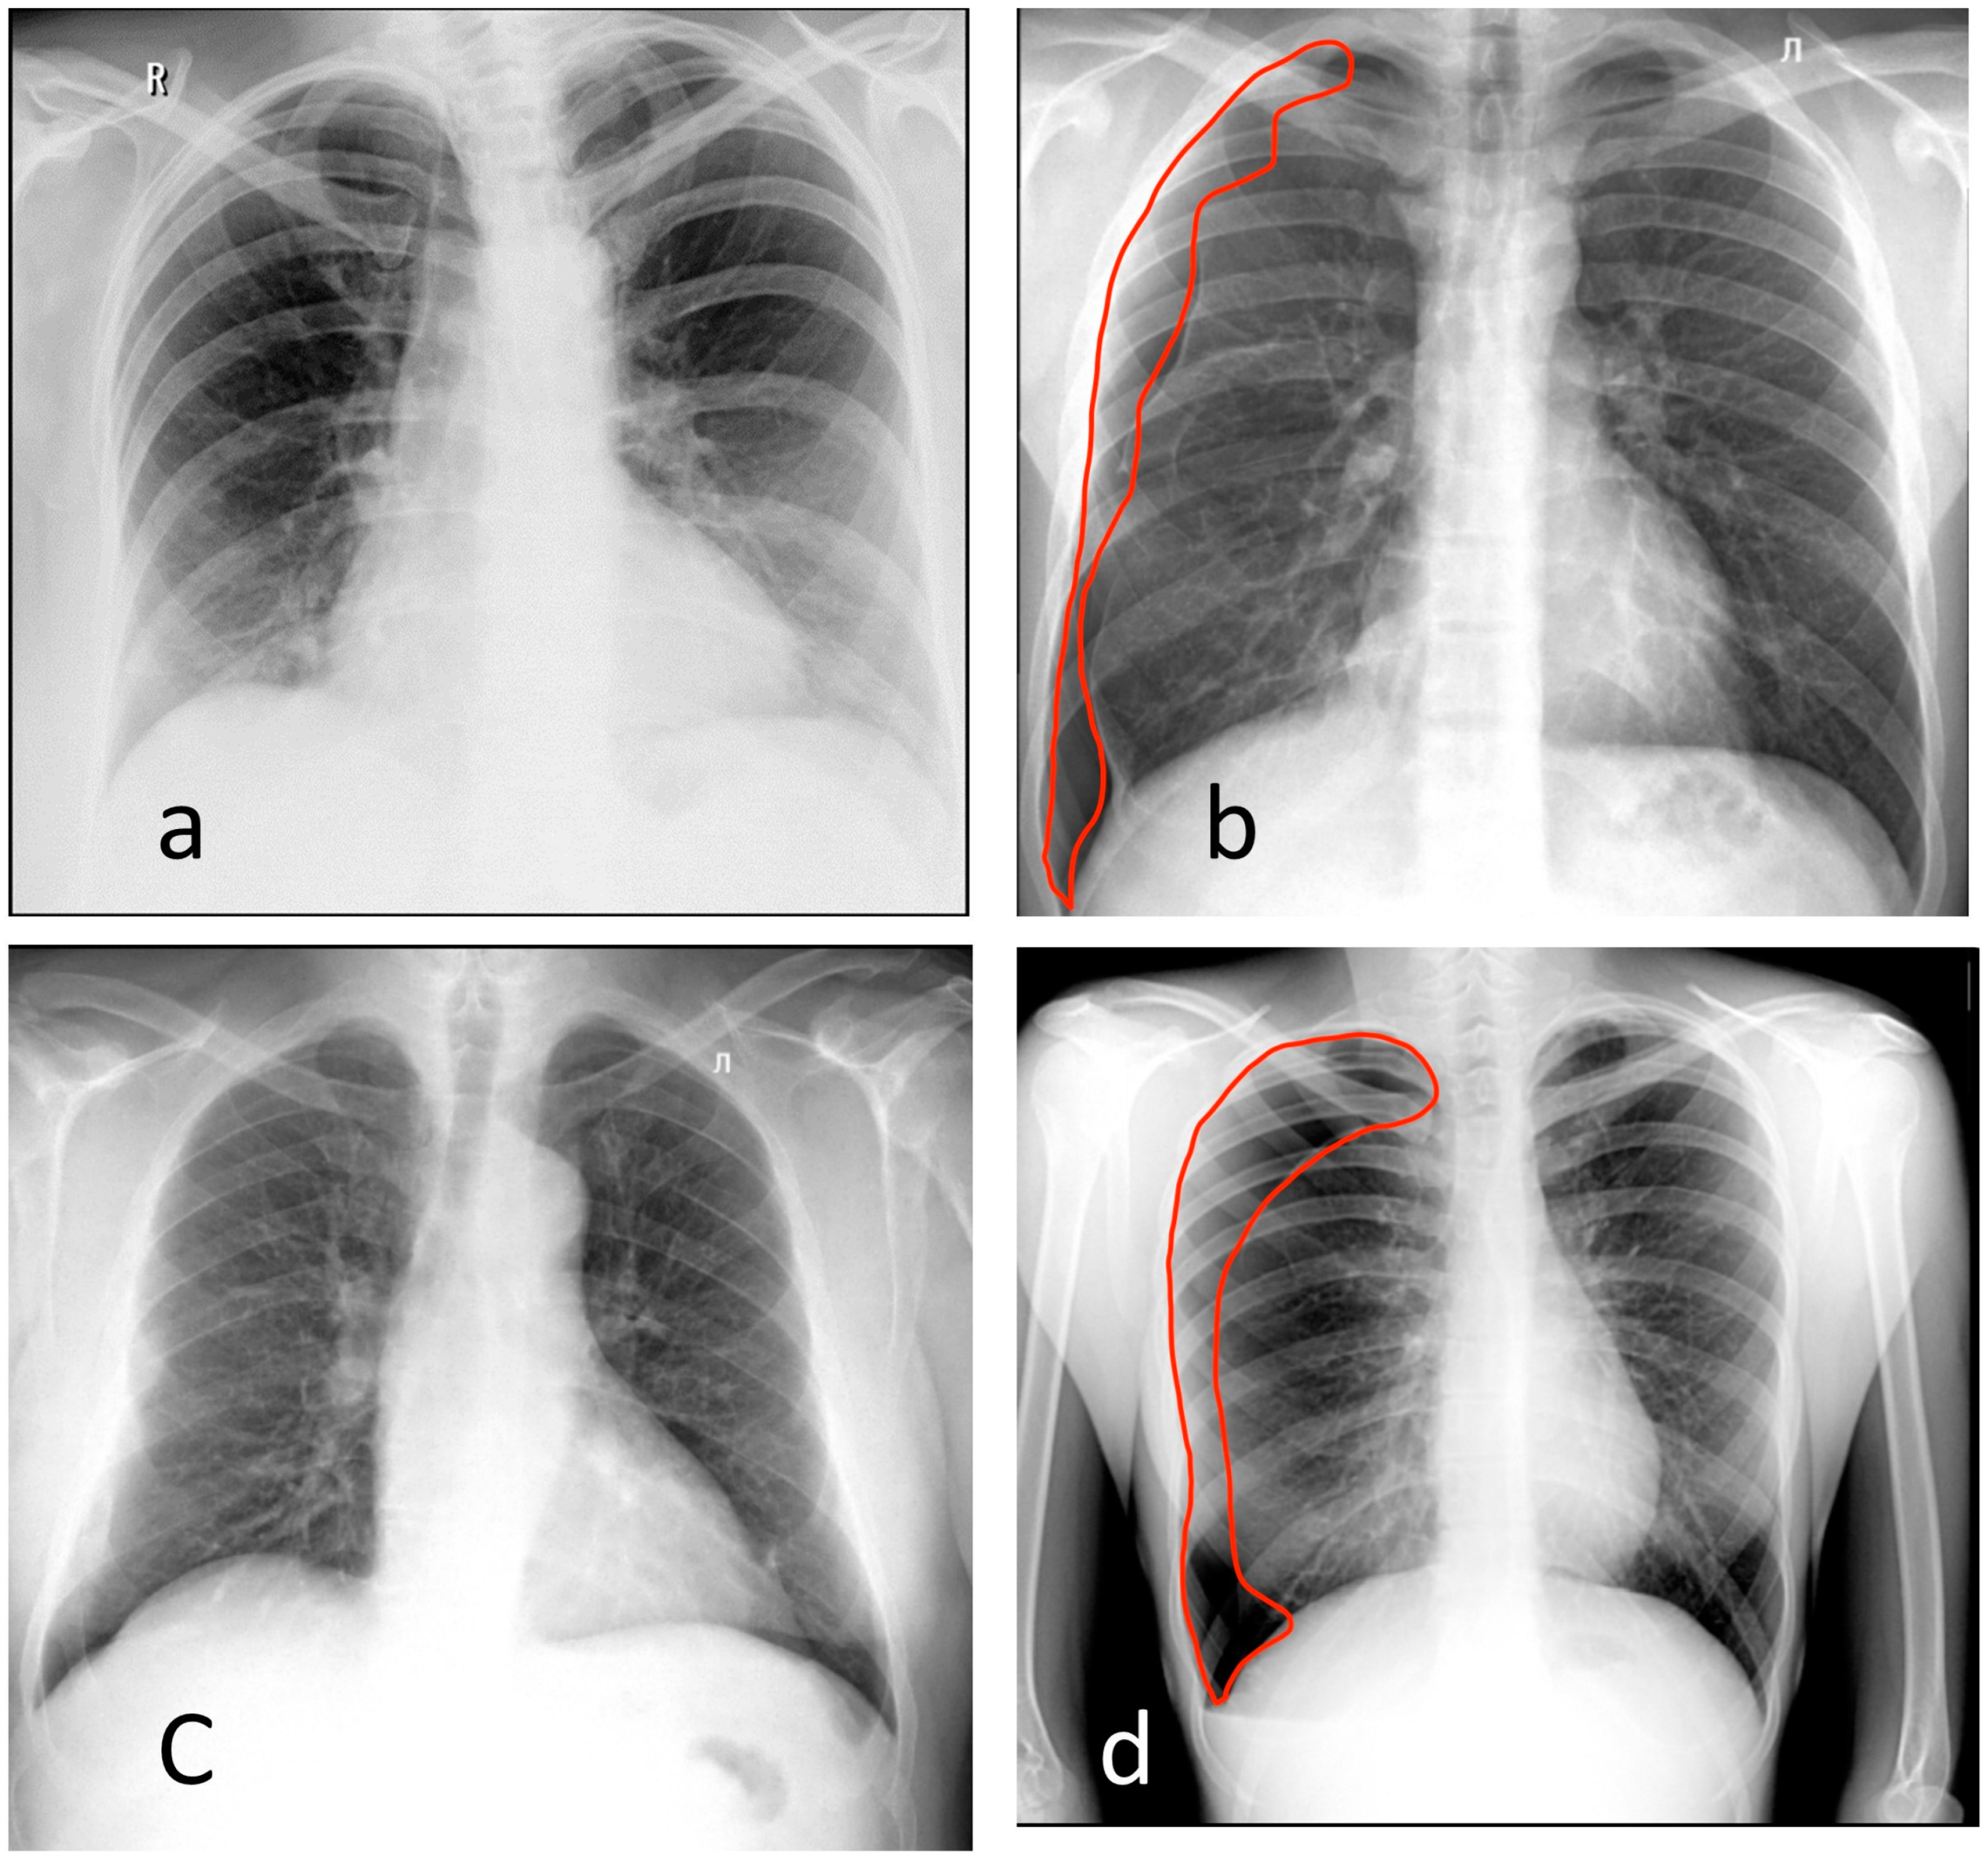

3.2. Chest Digital Fluorography (FLG)